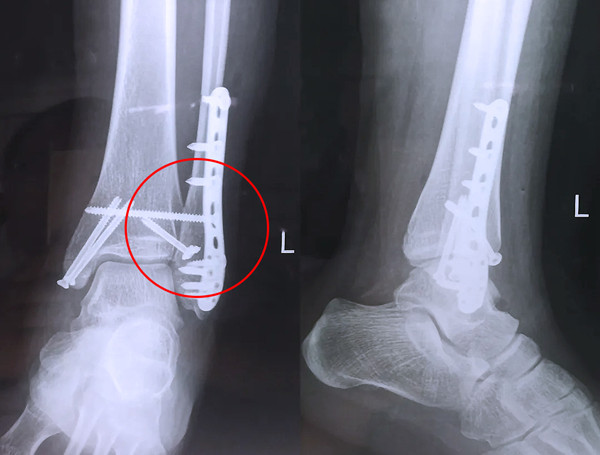

踝關節骨折在X影像上的表現有很多種。如內踝骨折和外踝骨折,我們可以在影像上看到骨折處的骨折線是不連續的。還有后踝的骨折,內踝、外踝、后踝聯合在一起發生的骨折,我們稱之為“三踝骨折”,這些都是在X影像上能夠顯示出來的。

三踝骨折

【醫療科普】Pilon骨折

有一種特殊類型的踝關節骨折,可能在X影像平片上就不能顯示出來,它就是脛骨的關節面往里塌陷,我們又稱之為叫“Pilon骨折”。當它往里塌陷后,我們在X影像平片上可能看不出來它是否塌陷,但是我們在CT上可以360°看到踝關節的影像,這樣就可以看出患者是否存在踝關節塌陷的骨折。同樣道理,我們在做Pilon骨折手術的時候,普通二維的X影像并不能判斷我們手術復位情況的好壞,這個時候如果醫生手上有能夠照三維影像的工具,那么對于醫生的準確手術是非常有好處的。